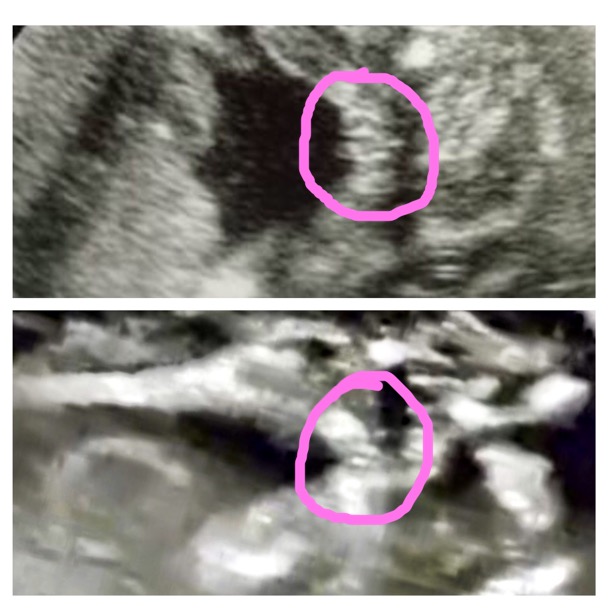

Can you please tell me if you see the same. Bottom photo is my scan, top is an internet photo. is labia visible in my bottom photo?

Attachment 34484